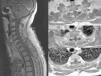

El sarcoma de Ewing es un tumor óseo maligno que en ocasiones presenta afectación extraesquelética, siendo rara la localización epidural. Presentamos el caso de una mujer de 45años que presentó parestesias, debilidad progresiva y retención urinaria. La resonancia magnética mostró una masa epidural desde C6 a D3. Se realizó una laminectomía de C7 a D2 y exéresis parcial de la lesión. El estudio anatomopatológico fue compatible con sarcoma de Ewing. La paciente recibió quimioterapia y radioterapia, no existiendo evidencia de enfermedad a los 8meses de seguimiento. Presentamos una revisión de la literatura de todos los casos publicados de sarcoma de Ewing extraesquelético con afectación epidural.

Ewing sarcoma is a malignant tumour of the bone that sometimes presents extraskeletal involvement, with the epidural location being rare. We report the case of a 45-year-old woman with paresthesia, paresis and urinary retention. Magnetic resonance imaging showed an epidural mass from C6 to D3. Laminectomy from C7 to D2 and partial resection of the lesion was performed. Pathological analysis was consistent with Ewing sarcoma. The patient received chemotherapy and radiotherapy, without evidence of disease at 8 months follow-up. A review of the literature on all published cases of extraskeletal Ewing sarcoma with epidural involvement is presented.